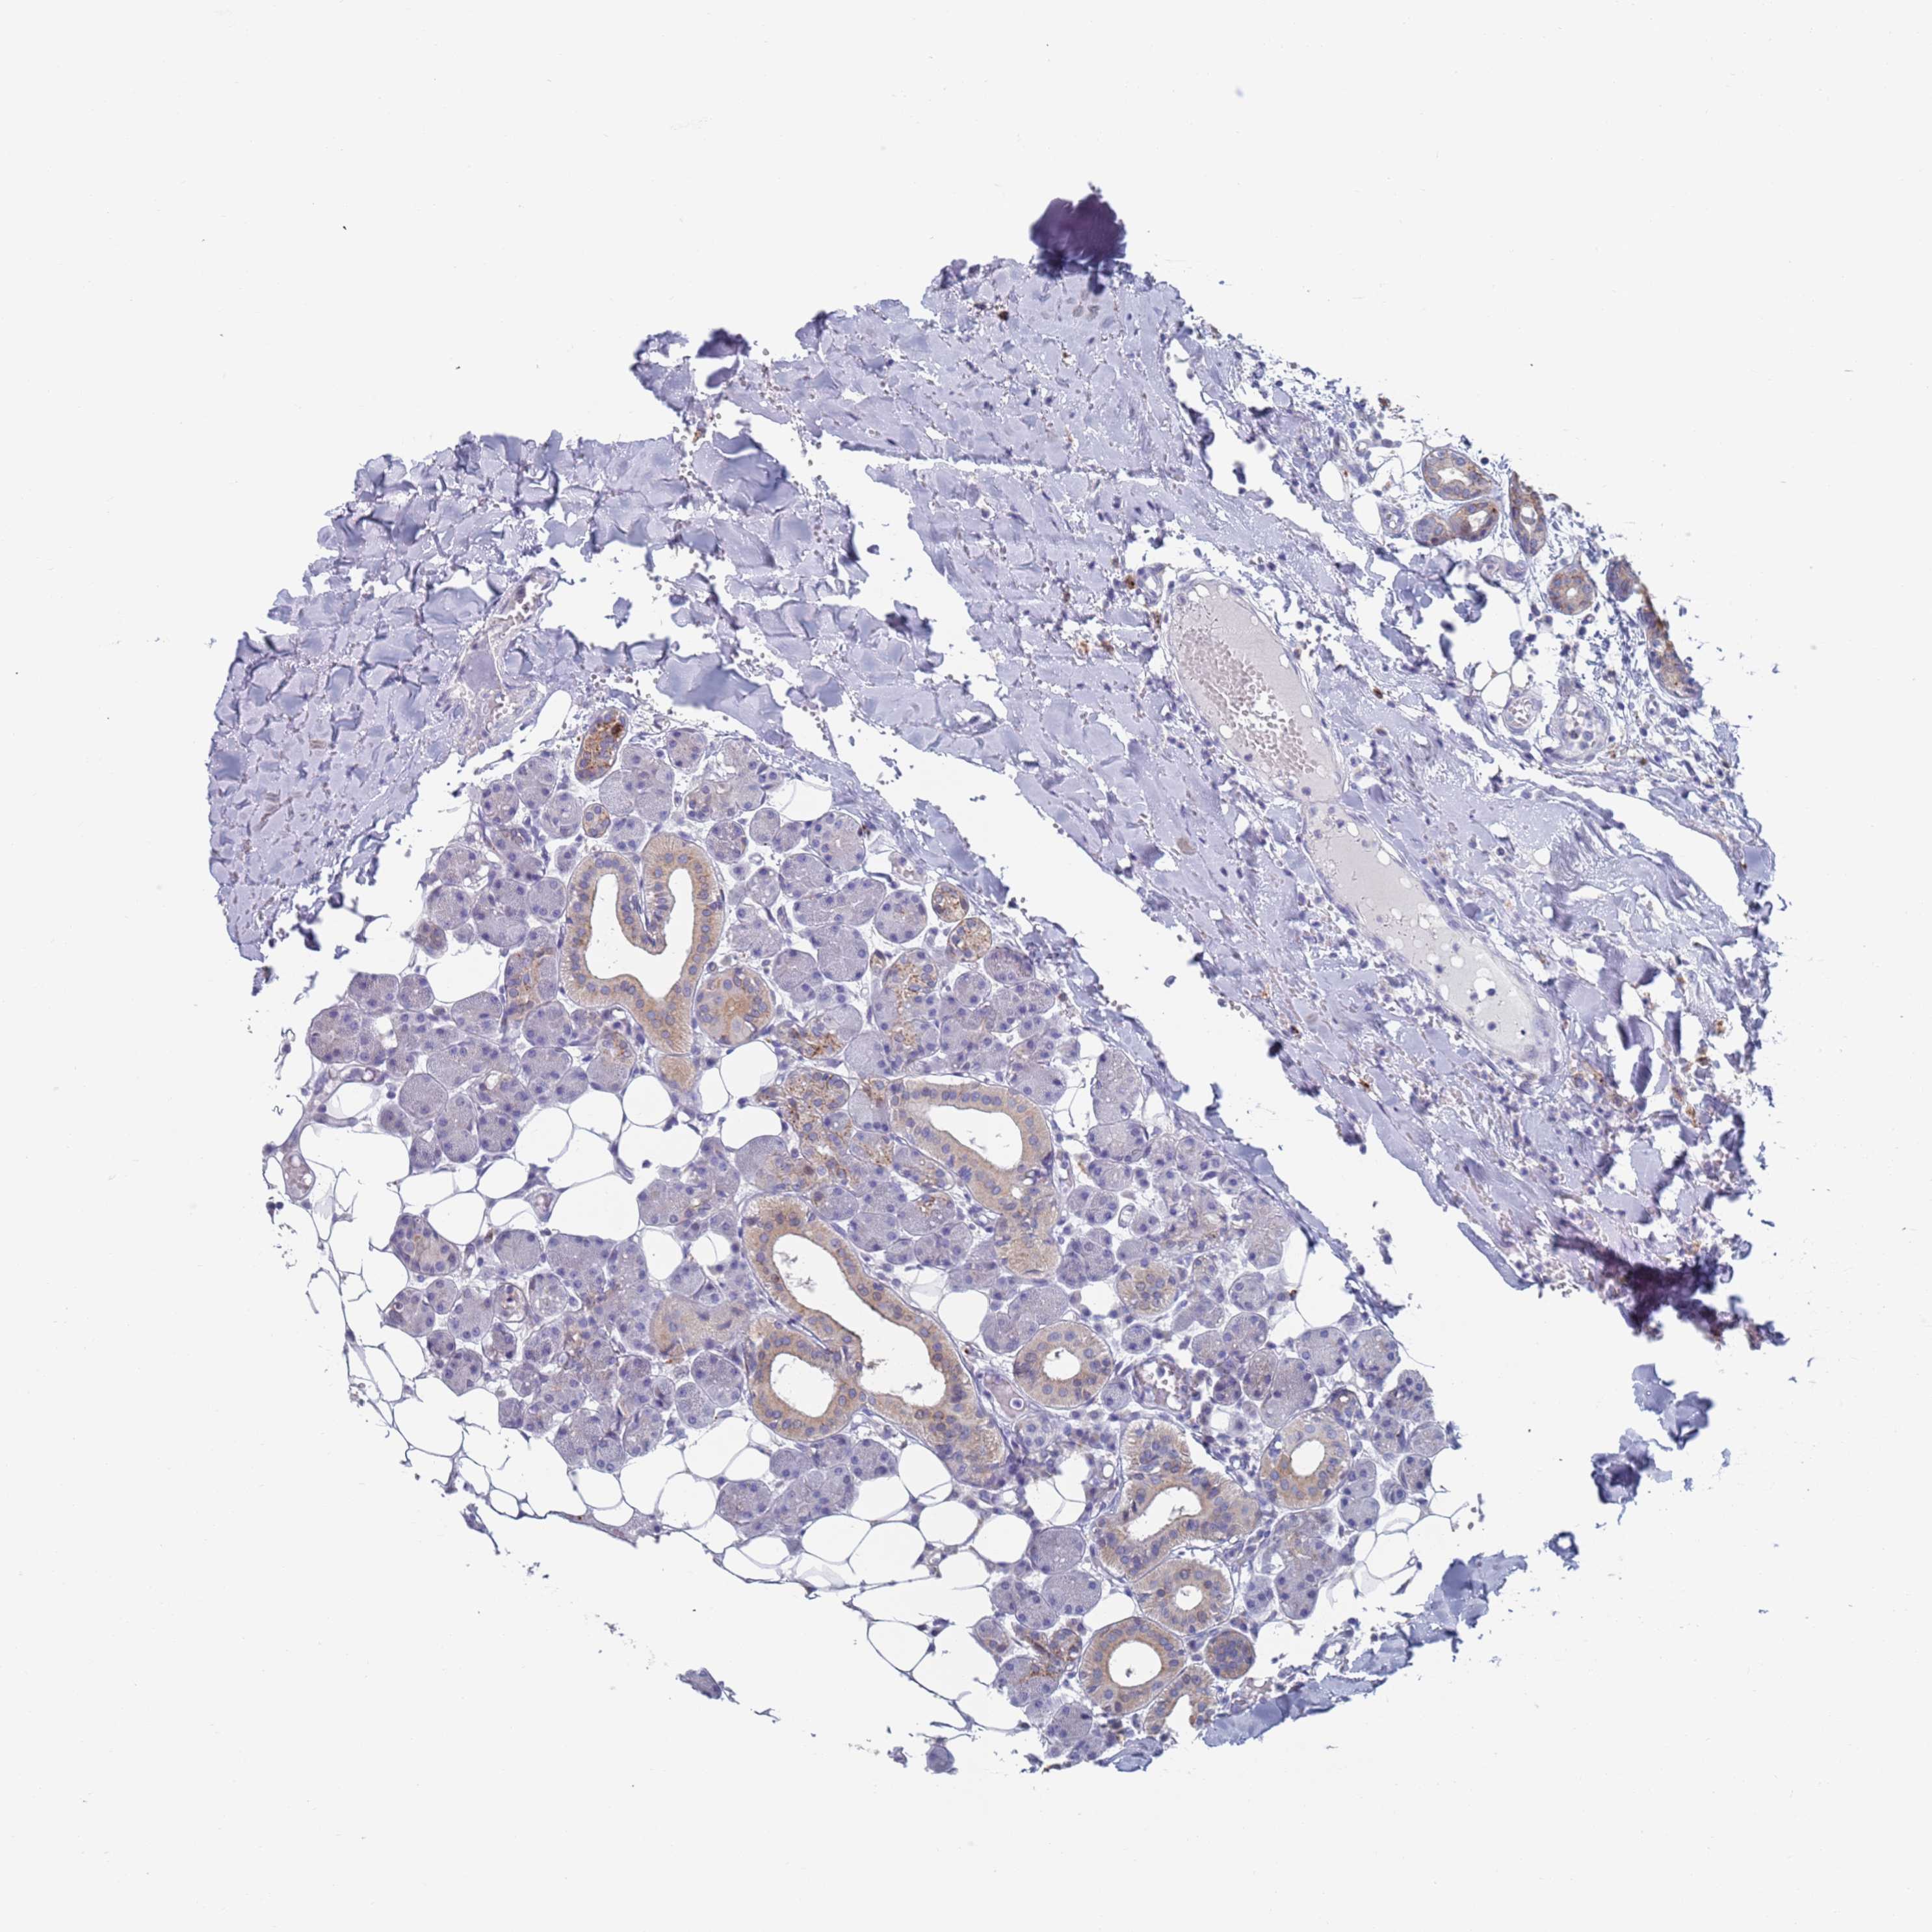

HEAD AND NECK CANCER - Protein expressioni

A mouse-over function shows sample information and annotation data. Click on an image to view it in a full screen mode. Samples can be filtered based on level of antibody staining by selecting one or several of the following categories: high, medium, low and not detected. The assay and annotation is described here.

Antibody stainingi

Antibody staining in the annotated cell types in the current human tissue is reported as not detected, low, medium, or high, based on conventional immunohistochemistry profiling in selected tissues. This score is based on the combination of the staining intensity and fraction of stained cells.

Each image is clickable and will lead to virtual microscopy that enables deeper exploration of all samples and also displays staining intensity scores, fraction scores and subcellular localization as well as patient and tissue information for each sample.

Antibody HPA046542

Staining

High

Medium

Low

Not detected

Intensity

Strong

Moderate

Weak

Negative

Quantity

>75%

75%-25%

<25%

None

Location

Nuclear

Cytoplasmic/membranous

Cytoplasmic/membranous,nuclear

Adenocarcinoma, NOS